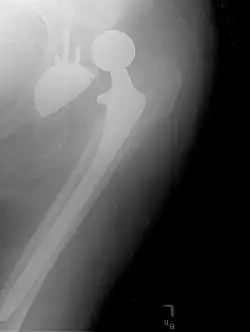

An X-ray showing a left hip (right of image) that has been replaced, with the ball of this ball-and-socket joint replaced by a metal head that is set in the femur and the socket replaced by a cup